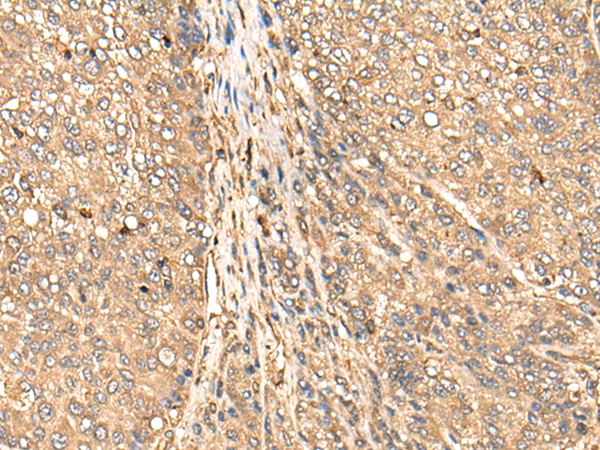

分类: 科研抗体货号: P09347别名: IRTKS应用: WB,IHC反应种属: Human, Mouse, Rat